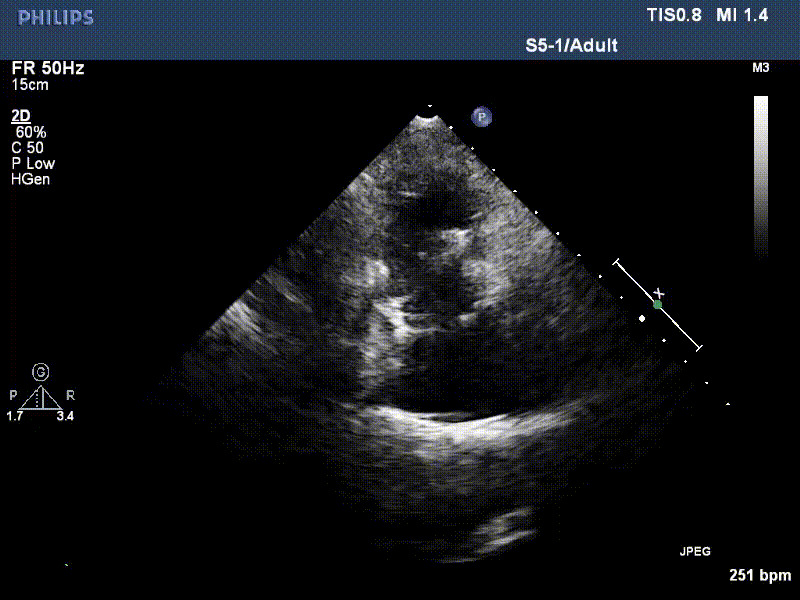

流并分別伴有房顫和房撲,高外科手術風險。術前超聲提示,兩例患者下腔靜脈寬度分別為13mm和29mm,右房內(nèi)徑(上下徑和左右徑)分別為52×41mm和53×43mm,彩色多普勒顯示極重度三尖瓣反流,VCW分別為14×15mm和10mm。

1年前,兩例患者因難治性雙下肢水腫輾轉多家醫(yī)院尋求救治,考慮到兩例患者高齡、基礎疾病多、STS評分高,不適合傳統(tǒng)外科開胸手術,葛均波院士及其團隊周達新教授、潘文志教授、張源博士、陳莎莎博士、陳丹丹博士聯(lián)合心外科王春生、魏來主任,麻醉科繆長虹、郭克芳主任以及心超室的潘翠珍教授、李偉教授共同討論決定,采用我國創(chuàng)新器械LuX-Valve Plus經(jīng)血管三尖瓣置換系統(tǒng)為患者進行手術。相較于第一代產(chǎn)品LuX-Valve,LuX-Valve Plus經(jīng)血管三尖瓣置換系統(tǒng)對輸送系統(tǒng)進行了全面升級,實現(xiàn)了經(jīng)頸靜脈入路的方式,進一步減小了手術風險和對患者的創(chuàng)傷。目前隨訪1年心超結果顯示,三尖瓣極重度反流消失,人工三尖瓣瓣膜穩(wěn)定牢固,瓣葉活動度良好,右心室及下腔靜脈明顯縮小,心輸出量增加。兩位老人手術后沒有出現(xiàn)過胸悶氣促的癥狀,下肢水腫緩解,活動耐力提升,生活質量也大為提高。

圖2 患者植入LuX-Valve Plus后,1年隨訪心超提示無三尖瓣反流